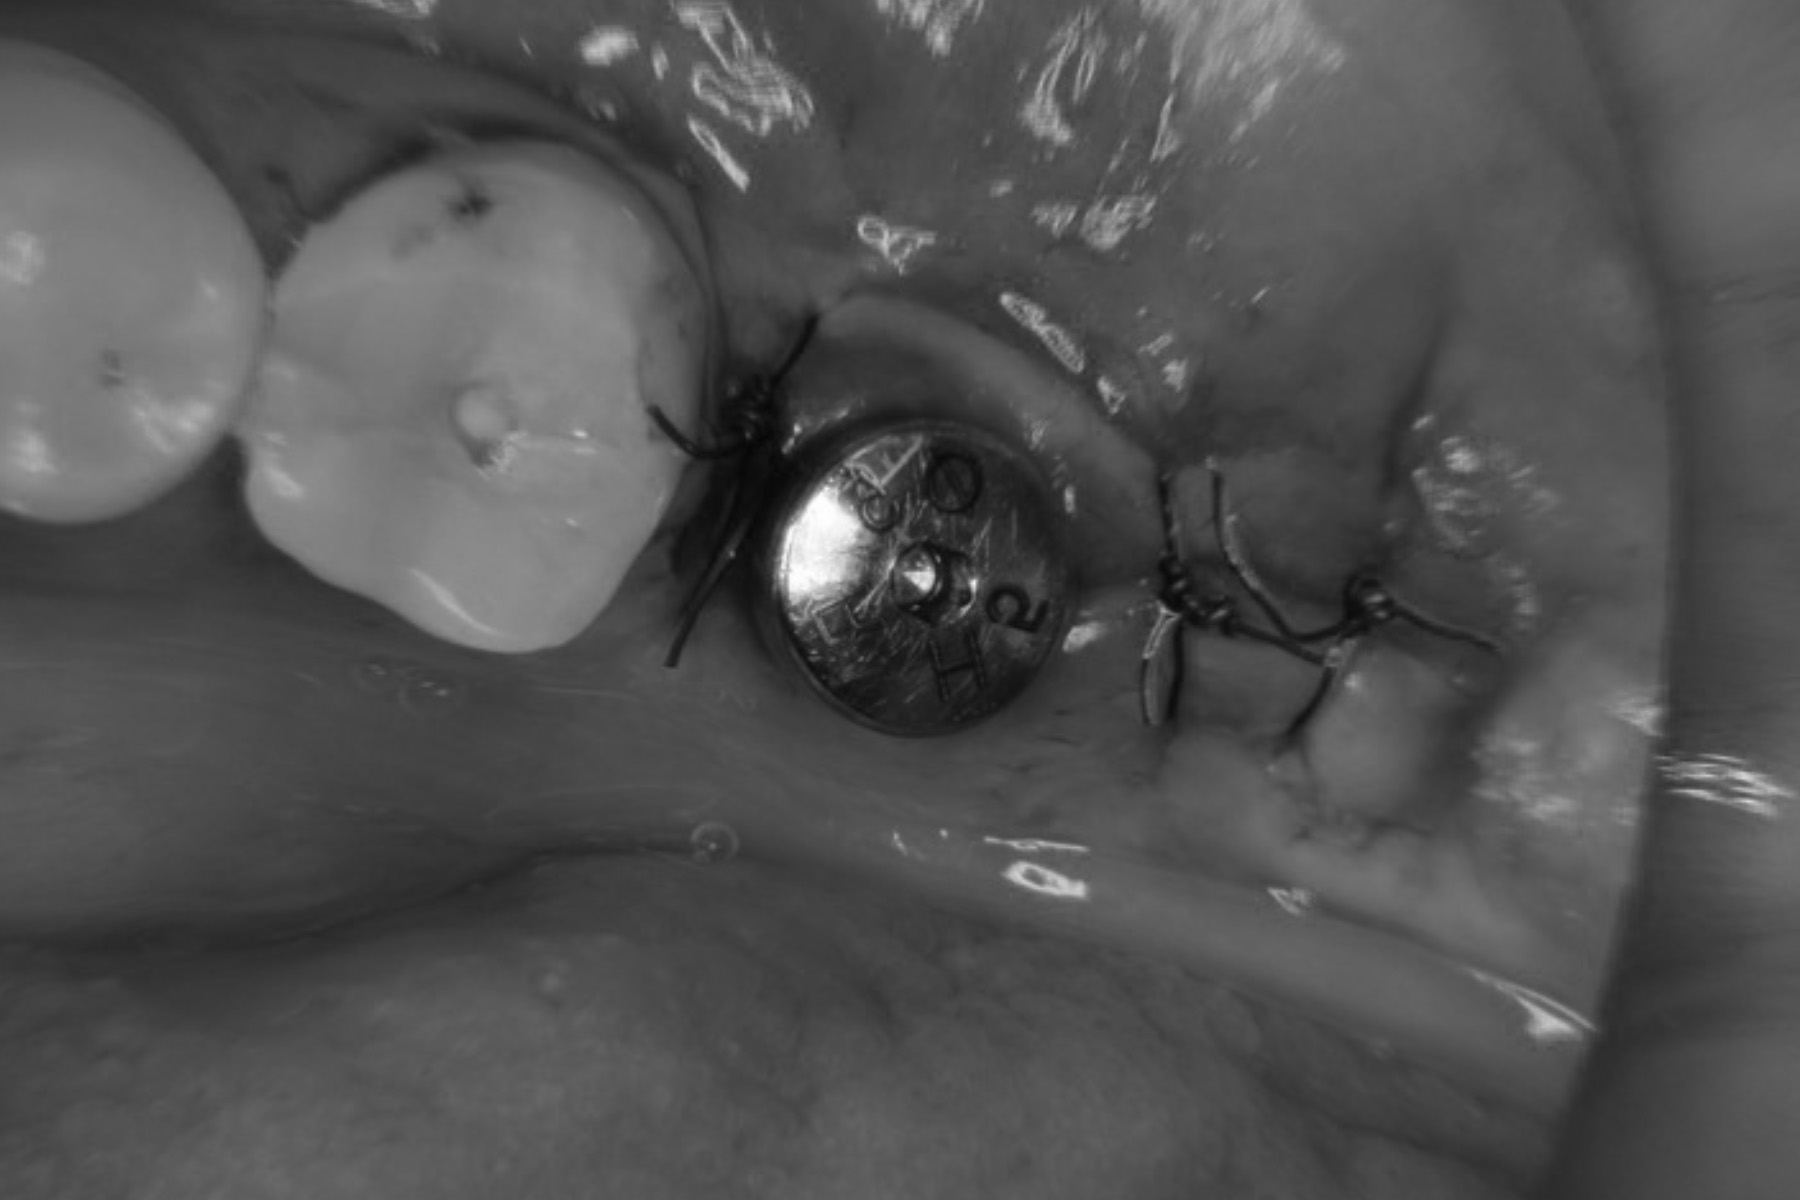

| 主訴 | 奥歯が腫れて膿んでいる |

|---|---|

| 治療内容 | 当該部歯牙は破折しており保存困難であった。抜歯と同時にインプラント埋入手術及び骨造成手術を全て同日に実施することにより手術回数を1度に抑え患者の負担を減らし、かつ通常6〜7ヶ月の治療期間を短縮した。 |

| 治療期間 | 3〜4ヶ月 |

| 治療費 | 約¥600,000〜¥700,000 |

| 治療リスク | 術後疼痛、腫脹。周囲組織の状態によっては追加の処置を要することもある。 |